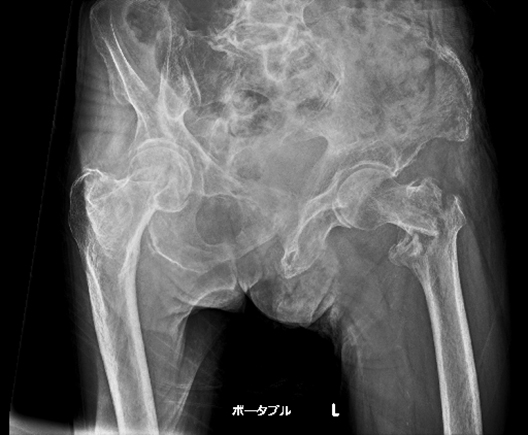

1例目は、89歳の男性で、基礎疾患として認知症、高血圧がある施設入所中の方です。ADLは歩行器歩行で、転倒されたという連絡を受けて、CALNEO Xairなどの撮影システム一式を持って訪問しました。そして、X線撮影を行うと、左の大腿骨の骨折が確認できました。(写真2)

X線撮影前の患者さんの反応だけでも骨折の可能性が非常に高いと考えられる症例ではありましたが、その場でX線撮影を行い、大腿部の転子部骨折ということで、手術対応ができる中核病院に搬送を行いました。